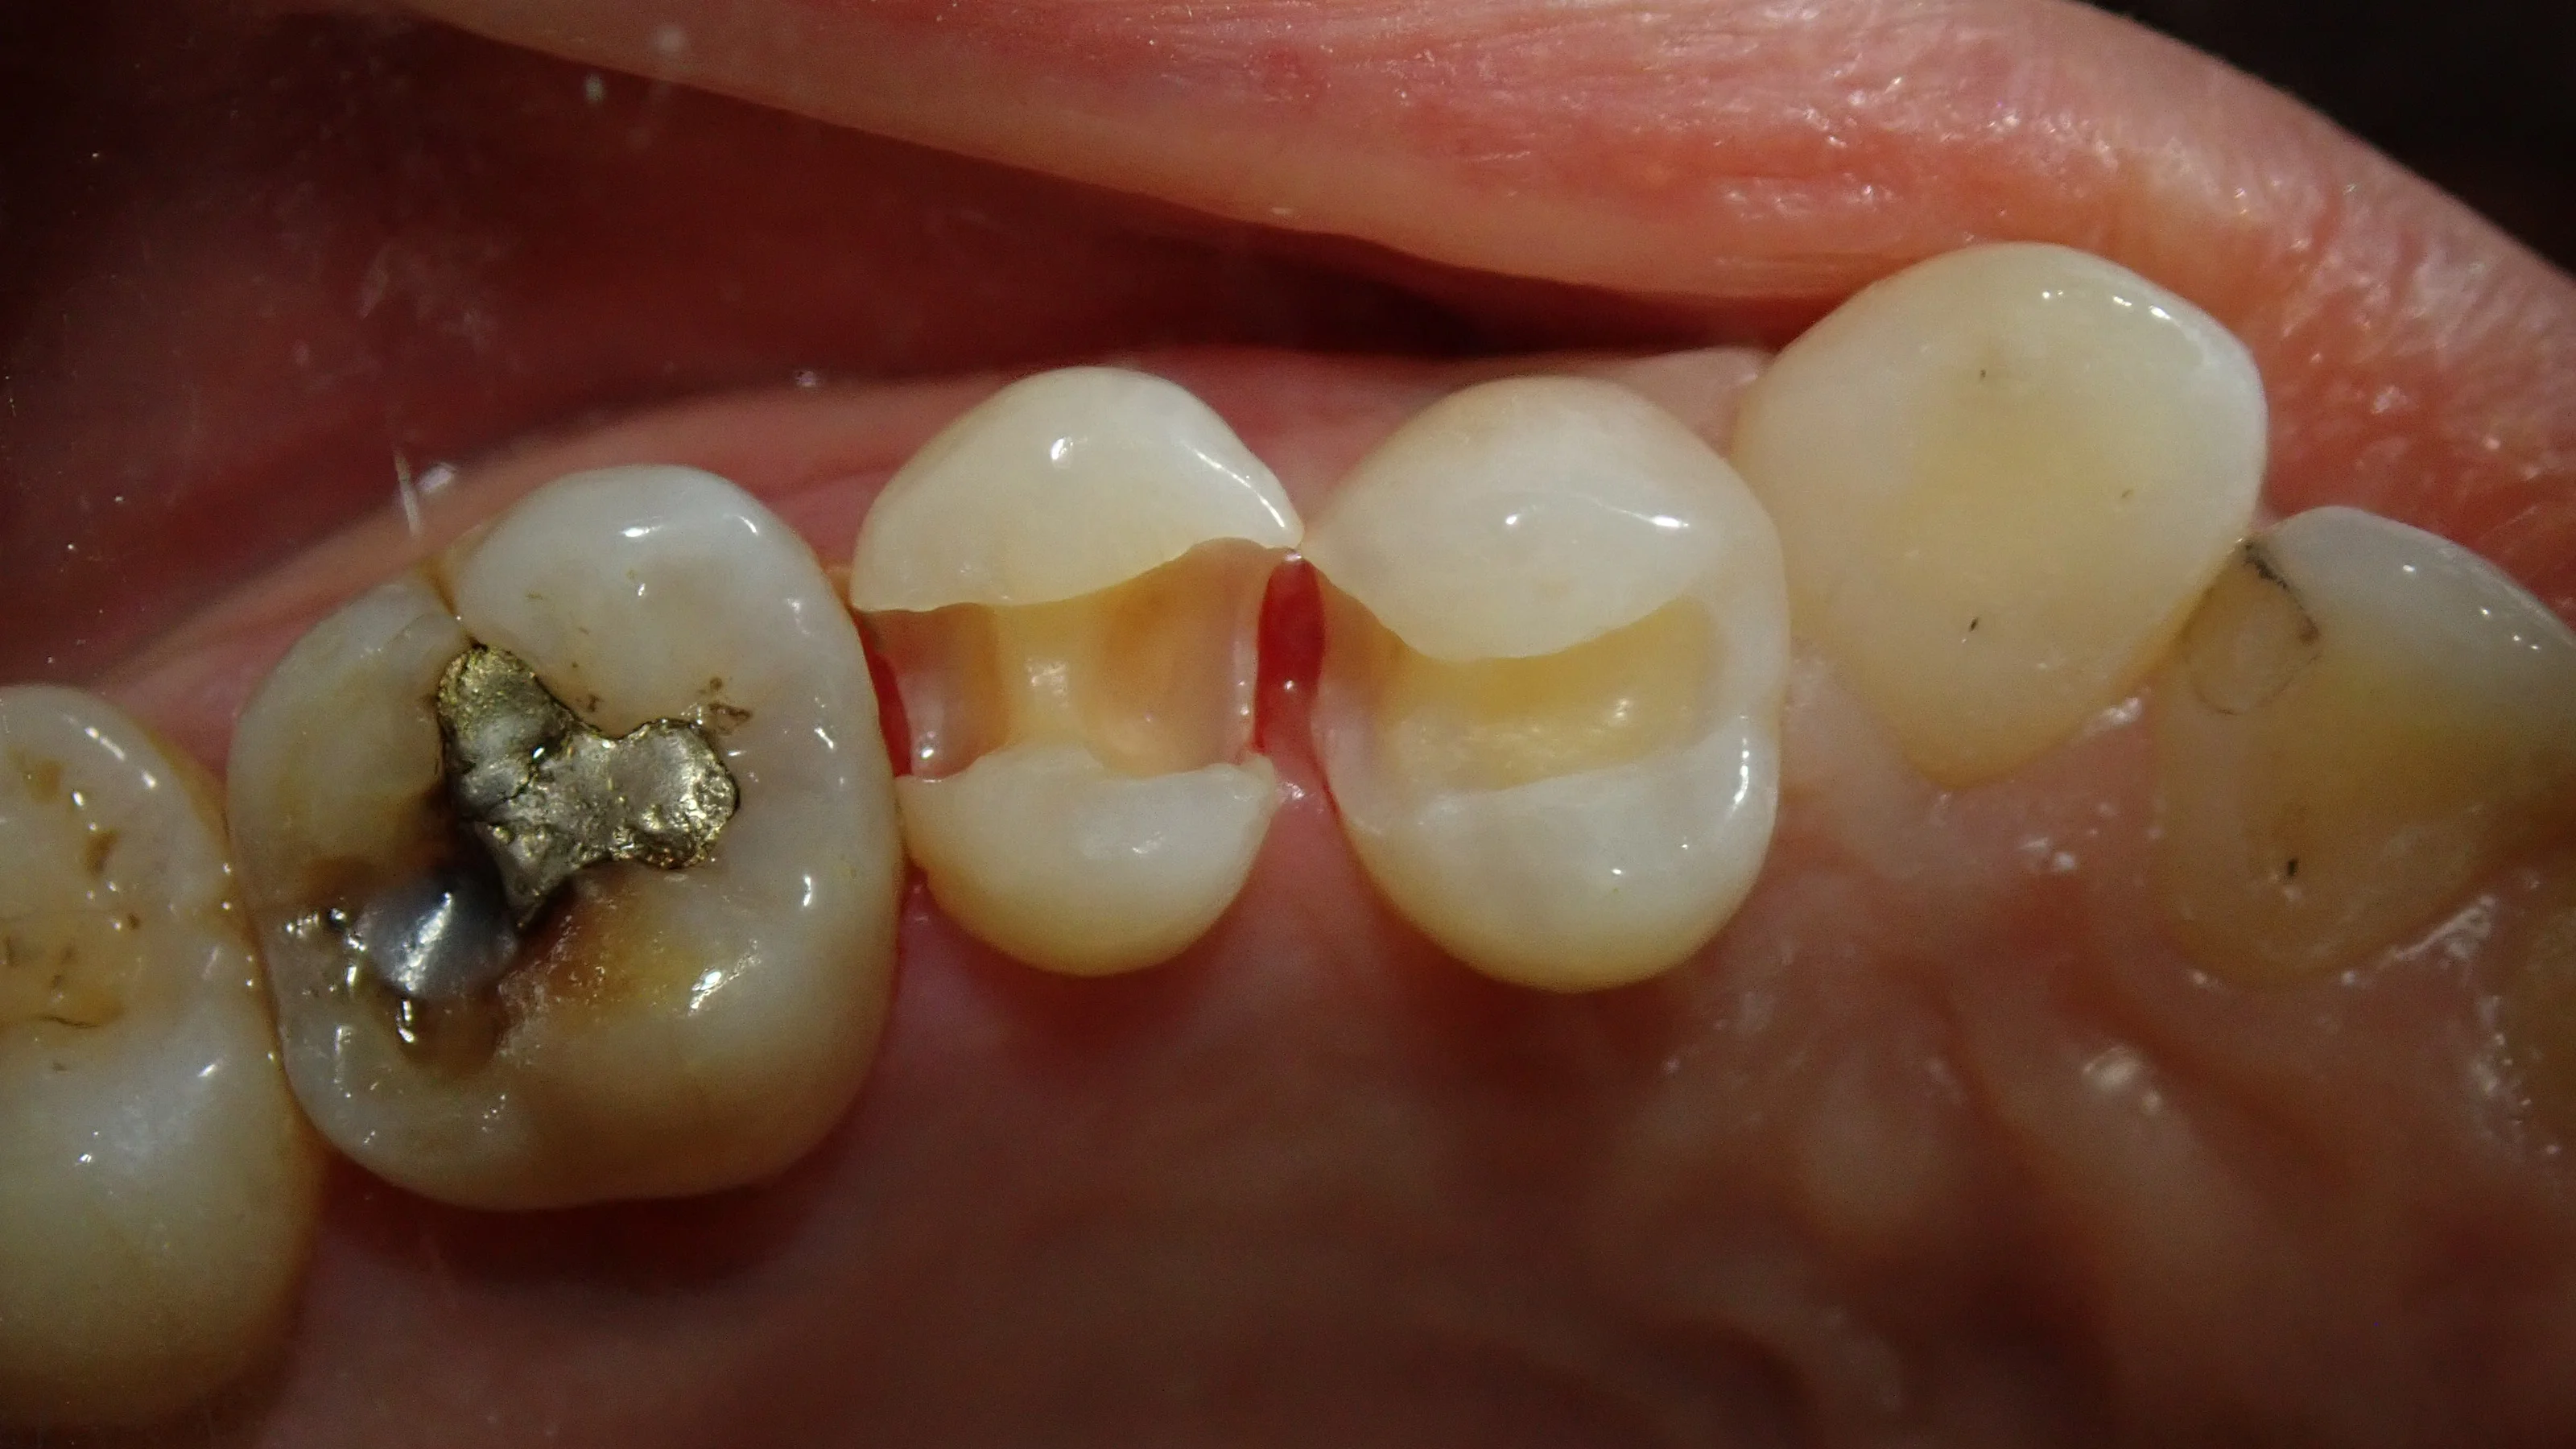

詰め物だけ完全に除去してみると、こうなりました。

左側の歯が、その更に奥の歯との間にも虫歯があることが分かりました。

どうせ費用も手間も変わりませんので、本人にもそのように説明後、そのまま虫歯を全て取り除きました。